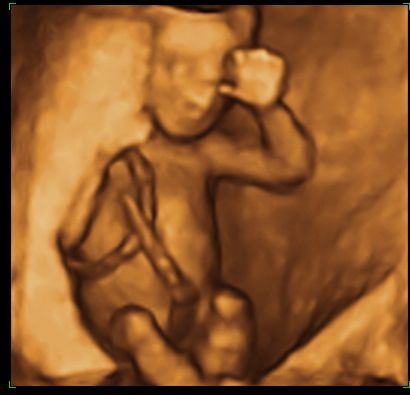

és néhány 4D-s kép:

Kép

Kép[img]

Naon szép a kislányod!És milyen helyes,hogy így integet! :lol:

Mintha csak kérted volna,hogy integessen!Legyen mindíg ilyen szófogadó! :lol: :lol: :wink: :wink:

És milyen jók a 4D-s képek is! :lol: :wink:

szép nagy pocak,és a 4ds képek annyira élethűek,nagyon jól lehet látni a pici vonásait,szép :)